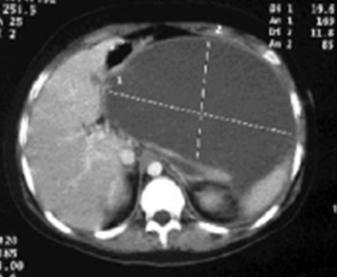

Megacolon tóxico

♦ Distensión y dolor abdominal

♦ Signos de sepsis (fiebre, taquicardia, hipotensión) y deshidratación

♦ Dilatación del colon (diámetro del colon transverso > 6 cm )

♦ Leucocitosis neutrofílica (> 10,500 / μL) y anemia Perforación → peritonitis

Figura 71. Megacolon tóxico. El colon transverso y el colon descendente carecen de rasgos distintivos, con pérdida de las marcas haustrales. El colon transverso está dilatado hasta un diámetro > 6 cm y son visibles algunos pseudopólipos.